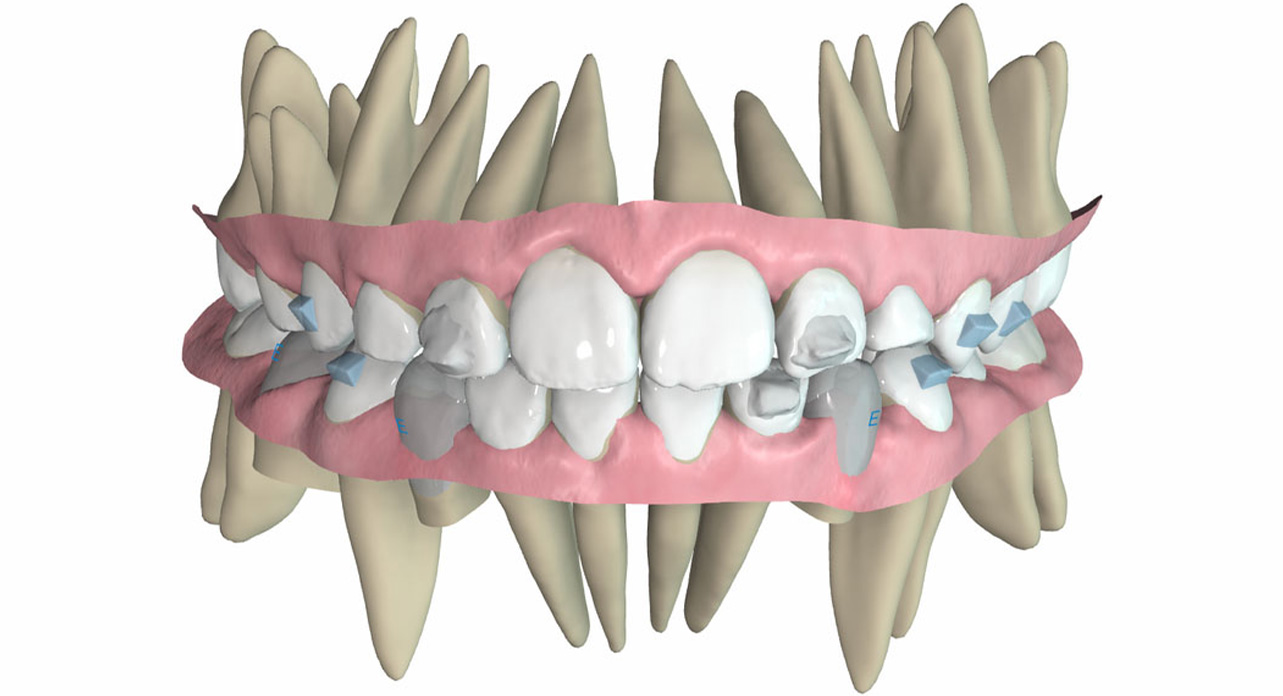

In the upper arch, the mechanics aimed to continue expansion of the first molars (6’s), while in the lower arch, the focus was on proclination of the lower incisors with lingual root torque. Simultaneously, the lower incisors were inclined towards the left side to correct the midline deviation.

Class II elastics were programmed, using hooks on the upper deciduous canines and Integrated hooks (IH) on the lower molars. The elastics were prescribed for 24-hour daily use, with a force of 3/16″ 4 oz. A virtual Class II elastic jump was requested from the technician.

It was critically important to plan for eruption compensators and retentive attachments to support the use of elastics effectively.

After completing the 14 aligners, records were taken for new aligners.

Proclination and intrusion of the upper incisors with palatal root torque, as well as proclination of the lower incisors with lingual root torque, were programmed to create overjet and allow for further mandibular advancement. The use of elastics was not necessary. Eruption compensators were planned.